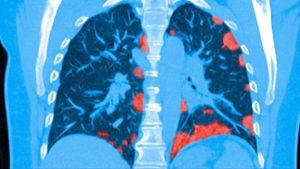

The threat is very real. Research proved that secondary infections (bacterial infections that develop in parallel with viral infections) can significantly increase the number of deaths in a virus outbreak.